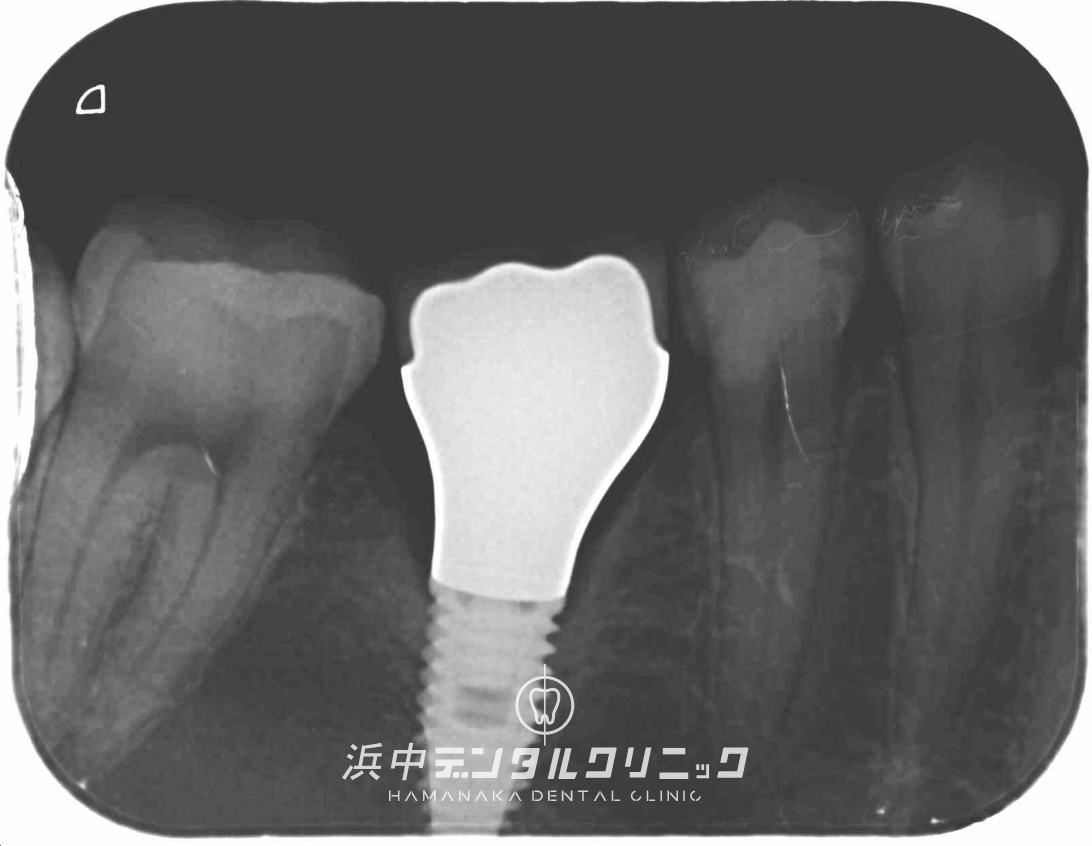

歯ぎしり・食いしばり(ブラキシズム)で歯が破折したので、抜歯後にインプラント治療した症例(60代女性)

BEFORE

AFTER

患者様の主訴

数日前から右下の奥歯が噛むと痛くなってきたので診てほしい。

診断結果

右下7番目の歯は患者様による歯ぎしり・食いしばり(ブラキシズム)による咬合力で破折しておりました。

治療内容

右下7番目の歯は保存不可だったので、残念ながら抜歯になりました。抜歯窩の治癒を待ってから、静脈内鎮静麻酔下でインプラント埋入手術を行いました。骨が足りなかったので埋入と同側の右側下顎枝から自家骨を採取して骨造成も同時に行いました。初期固定が35ニュートンありましたので同時にインプラント土台のOn1アバットメントの装着も行いました。インプラントが骨と生着後に仮歯の型取りを行い、その後仮歯を装着して約3ヶ月間使用していただき問題がありませんでしたので、最終補綴物(ジルコニアセラミック)を型取りして数回の試適などを行いスクリューリテインの最終補綴物(ジルコニアセラミック)を装着して治療が完了しました。

治療後経過

インプラント治療終了後から約5年経過していますが全く問題なく経過良好です。

| 治療期間 | 約8ヶ月 |

|---|---|

| 治療にかかった費用 | インプラント体(フィスクチャー308,000円)×1本 +インプラント土台(アバットメント77,000円)×1本 +インプラント人工歯(上部構造ジルコニアセラミック165,000円)×1本 +骨造成術(GBR)220,000円 +静脈内鎮静麻酔77,000円 +仮歯代22,000円×1本分 |

| リスク副作用 | インプラントは入れたら終わりではなく、きちんとメンテナンスしないと歯周病になることもあるので、定期的にクリーニングや噛み合わせの調整が必要です。 |